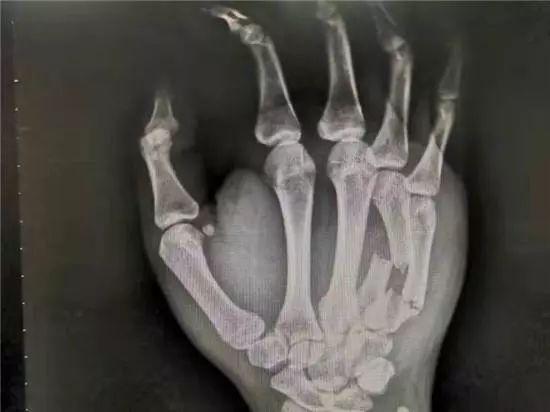

1 月 6 日下午和 1 月 7 日晚上,李兴源和张远在跟女友吵架后,情绪激动,气愤难耐,却又无从发泄,一怒之下,只能使劲握拳捶打墙面,结果猛力捶打过后,手掌剧痛伴畸形和无法用力急诊入院。根据急诊 X 线检查提示,两人均诊断为 " 右手第 4-5 掌骨骨折 "。被收入南华大学附属长沙中心医院创伤手外科住院后,蒋亮东医生先后为他们进行了右手第 4-5 掌骨骨折切开复位内固定术,术后恢复良好。